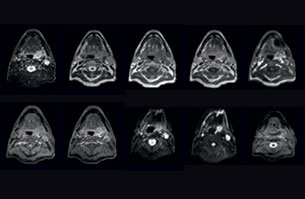

Visualizing critical structures in the head and neck

“In patients with a primary tumor in the head and neck area, we do use MRI in daily clinical radiation therapy practice to visualize the tumor and critical structures. This may be used to help sparing of critical structures, such as the parotid glands, submandibular glands, esophagus, optic nerves, brain stem and spinal cord [7]. And postoperatively we scan patients that have tumor growth along the cranial nerves for target delineation,” says Dr. Philippens.

“Because of the challenges posed by CT-MRI coregistration in this area with many degrees of freedom for motion, we image these patients in a radiotherapy mask. However, one disadvantage of using the mask is that a regular head and neck coil cannot be used; a dedicated coil solution would be needed for imaging with a mask.

For this we make use of flexible coils that we position close to the target area. This setup can also be combined with the anterior coil for a larger coverage and enhanced SNR.”

“We use pre- and post-contrast T1- and T2-weighted sequences with the fast and robust mDIXON method for fat suppression,” says Dr. Philippens. “Dynamic contrast-enhanced imaging is performed with high temporal resolution and low spatial resolution, to see the contrast agent uptake in the tumor. Diffusion weighted imaging is used qualitatively to see how the tumor extends into another structure, rather than for strict delineation.”

“In postoperative patients who have had tumor growth along the cranial nerves, we use T2-weighted gradient echo (FFE) on our 3.0T MR-RT scanner to show the nerves for target delineation and look to see if there is still tumor left.”